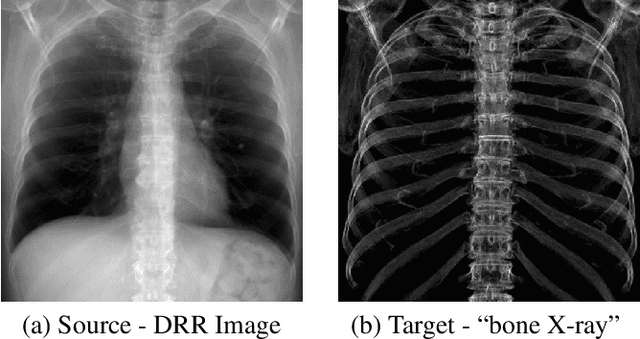

Abstract:In this paper, we present a deep learning-based image processing technique for extraction of bone structures in chest radiographs using a U-Net FCNN. The U-Net was trained to accomplish the task in a fully supervised setting. To create the training image pairs, we employed simulated X-Ray or Digitally Reconstructed Radiographs (DRR), derived from 664 CT scans belonging to the LIDC-IDRI dataset. Using HU based segmentation of bone structures in the CT domain, a synthetic 2D "Bone x-ray" DRR is produced and used for training the network. For the reconstruction loss, we utilize two loss functions- L1 Loss and perceptual loss. Once the bone structures are extracted, the original image can be enhanced by fusing the original input x-ray and the synthesized "Bone X-ray". We show that our enhancement technique is applicable to real x-ray data, and display our results on the NIH Chest X-Ray-14 dataset.